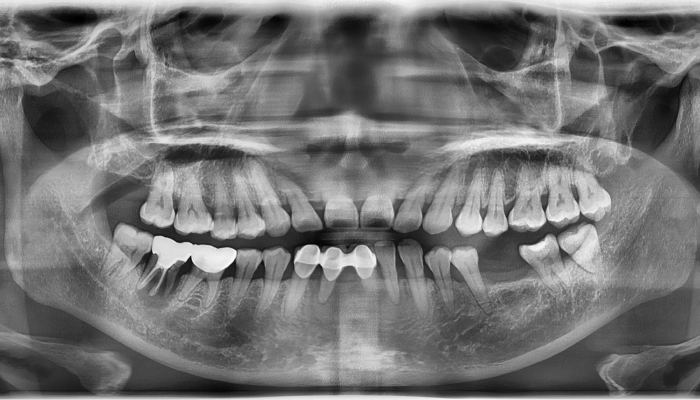

뼈이식 임플란트 전후 사례

• 식립전

식립후